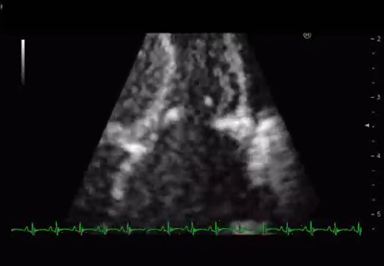

心臓超音波検査では,治療開始2週間で三尖弁逆流が軽減した.入院時TRPG=69 mmHgとoversystemic PHの状態あったが,徐々にTRPGが低下し,PHの改善が見られた.右室圧の低下に伴って左室は円形となり左室拡張末期径は,17.2 mmから21.0 mmに改善が得られた.左室扁平度は,入院時0.36,治療開始~退院時0.68,退院後フォロー時1.07と改善した8)

その後,MS・MRが改善し,入院1か月で,MRはmoderate,1か月半でmildまで改善した.MSに関してはtransmitral flowはE peak velocityが2.26 m/secから1.50 m/secまで低下し,Pressure half timeの延長も改善した.僧帽弁尖の肥厚や輝度上昇は変化がなかったが,coaptation depthは6.6 mmから2.1 mmまで改善し,coaptation heightも2.7 mmから5.5 mmまで改善した(Table 2, Fig. 3).

遠隔期評価

1歳6か月で状態把握のための精査目的に入院した.身長78.8 cm,体重9,120 gと発育に問題なく,独歩可能で発語もあり発達にも異常は認めなかった.胸部レントゲンでは心胸郭比は45%と正常で12誘導心電図でも正常洞調律で負荷所見は認めなかった.

心臓超音波検査では,左室流入血流はE peak velocity 1.2 m/secまで改善し,Pressure half timeの延長もなかった.僧帽弁の弁口面積は1.49 cm2と充分な開口でありMSの所見は認めなかった.

僧帽弁前尖の逸脱を認め,MRはmild-moderate残存していたものの,心臓カテーテル検査を施行し,平均肺動脈圧は16 mmHgと肺高血圧は認めず,肺動脈楔入圧は7 mmHgと正常であった.心拍出は熱希釈法でCardiac index=5.12 L/min/m2と正常心拍出であった.そのため,現在も手術適応とは判断せず,内科管理で経過をみている.